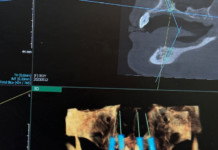

Синус-лифтинг: суть процедуры и показания к проведению

Синус-лифтинг — звучит немного страшно, правда? Но на самом деле это довольно распространенная и важная процедура в стоматологии, которая помогает многим людям вернуть красивую...